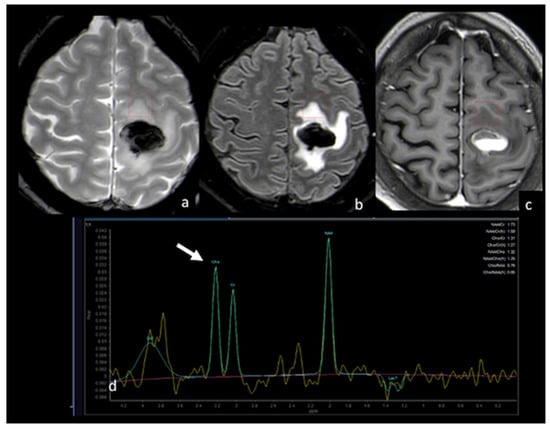

3.4. H-Magnetic Resonance Spectroscopy

- Chiang, I.C.; Kuo, Y.T.; Lu, C.Y.; Yeung, K.W.; Lin, W.C.; Sheu, F.O.; Liu, G.C. Distinction between high-grade gliomas and solitary metastases using peritumoral 3-T magnetic resonance spectroscopy, diffusion, and perfusion imagings. Neuroradiology 2004, 46, 619–627. [Google Scholar] [CrossRef] [PubMed]

- Bendini, M.; Marton, E.; Feletti, A.; Rossi, S.; Curtolo, S.; Inches, I.; Ronzon, M.; Longatti, P.; Di Paola, F. Primary and metastatic intraaxial brain tumors: Prospective comparison of multivoxel 2D chemical-shift imaging (CSI) proton MR spectroscopy, perfusion MRI, and histopathological findings in a group of 159 patients. Acta Neurochir. 2011, 153, 403–412. [Google Scholar] [CrossRef] [PubMed]

- Wijnen, J.P.; Idema, A.J.; Stawicki, M.; Lagemaat, M.W.; Wesseling, P.; Wright, A.J.; Scheenen, T.W.; Heerschap, A. Quantitative short echo time 1H MRSI of the peripheral edematous region of human brain tumors in the differentiation between glioblastoma, metastasis, and meningioma. J. Magn. Reson. Imaging 2012, 36, 1072–1082. [Google Scholar] [CrossRef] [PubMed]

- Ricci, R.; Bacci, A.; Tugnoli, V.; Battaglia, S.; Maffei, M.; Agati, R.; Leonardi, M. Metabolic findings on 3T 1H-MR spectroscopy in peritumoral brain edema. AJNR Am. J. Neuroradiol. 2007, 28, 1287–1291. [Google Scholar] [CrossRef]